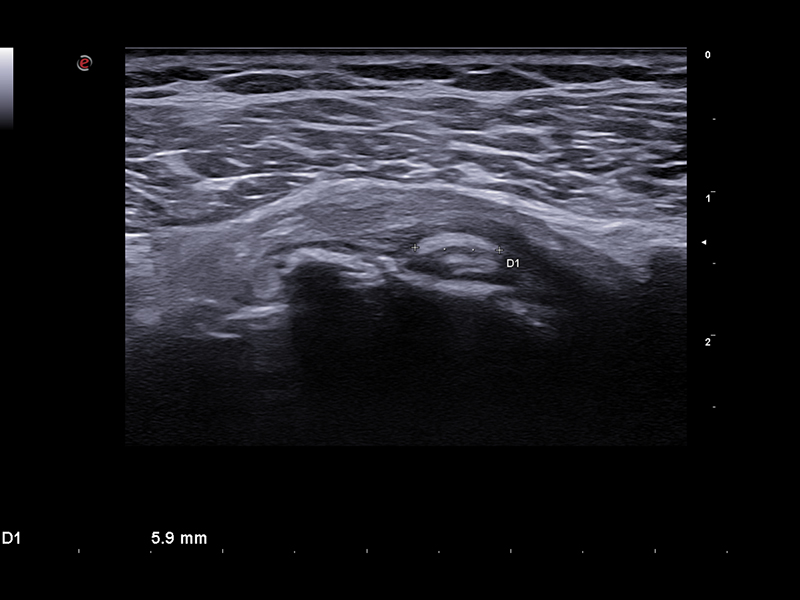

Over the past years, huge improvements in image quality have been achieved, such as broadband transducer technology (up to 25 MHz), harmonic and compound imaging, improved focusing, beam steering, and Power Doppler imaging.

Imaging plays a crucial role in musculoskeletal applications. A genuine technological breakthrough in very superficial explorations, the LMX 4-20, Esaote’s brand-new HD Single Crystal probe, which is operating up to 25 MHz, offers unprecedented clarity even in the smallest details without compromising the deeper areas. Applied to this high-density element per multi-layer matrix structure array, XCrystal Technology enables unparalleled sharp and clear imaging to achieve excellence in superficial ultrasound examinations, and becomes the Esaote gold standard in terms of linear probes.

The use of our latest Very-High Frequency Hockey Stick probe, IHX 6-25, delivers outstanding spatial resolution while facilitating needle access to perform accurate interventional gestures with millimetric precision.